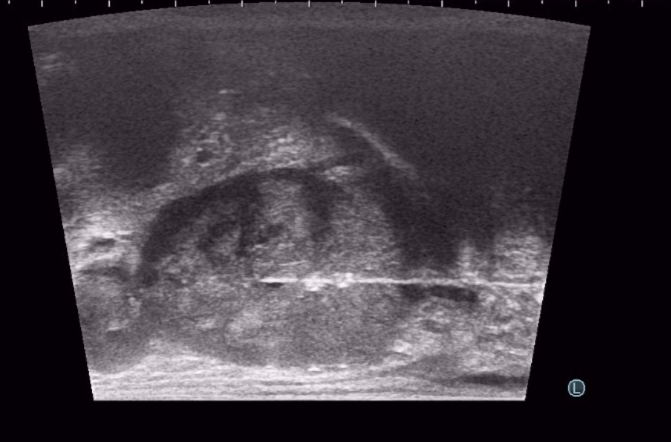

TP prostat biyopsisi, yani temiz prostat biyopsisi, hastanın isteğine göre, lokal uyuşturma ile, ya da kolonoskopideki gibi sedasyon dediğimiz hafif uyutma ile yapılabilir.  TRSU biyopsiden farklı olarak, temiz prostat biyopsisinde hastaya sedyeye sırtüstü yatırılır ve bacakları iki yana-yukarı doğru açılır. Biyopsi sırasında iğne makattan geçmez, ama ultrason görüntüsü almak için yine makata ince bir ultrason başlığı yerleştirilir.  Doktor, kaydırıcı ve uyuşturucu özellikleri olan bir jeli hastanın makat bölgesine sürer. Daha sonra, prob adı verilen ince ultrason başlığını yavaş bir şekilde hastanın makat bölgesine yerleştirir. Hastamız kendisini gevşek bırakır ve makat bölgesini sıkmazsa, başlık hiç rahatsızlık vermeden, yumuşak bir şekilde içeri doğru ilerler. Kendisini sıkan hastalarda bile, zorlama yapılmadan yavaş davranılırsa, makat girişi bir süre sonra gevşeyerek başlığın acısız bir şekilde girmesine izin vermektedir. Çok nadiren (yaklaşık %1), makat girişinde darlık ya da yarası olan hastalarda bu aşamada ağrı olabilir. Bu durumda hastanın canını acıtarak işleme devam etmeyiz. İşlem hasta uyutularak, anestezi altında yapılır.

Başlığı makat bölgesine yerleştirdikten sonra, Ultrason’da prostat, TRUS biyopsi ultrason cihazından daha da net  bir şekilde görülür. Bundan sonra, çok ince bir iğneyle perine adı verilen, makat ile yumurtalıklar arasındaki cilt bölgesine uyuşturucu ilaç verilir. Cilt uyuştuktan sonra aynı ince iğne daha içeri doğru ilerlenip, prostatın çevresine de uyuşturucu ilaç (lokal anestezi) yapılır. Böylece giriş alanı ve prostatın tamamı uyuşur ve işlemin bundan sonraki kısmını hasta en fazla sinek ısırığı gibi hafif bir acı olarak hisseder. Bu aşamada, ülkemizde çok az merkezde uygulanan, koaksiyel iğne ile biyopsi işlemini yapmaktayız. Ülkemizde birçok merkezde TP prostat biyopsisi yapılmaktadır. Ancak çoğunda, prostattan alınacak her parça için iğne perine adı verdiğimiz bölgeye tekrar tekrar girip çıkmaktadır. Bu da hem hastaya ağrı vermekte, hem de yan etki risklerini arttırmaktadır. Bu yöntemle yapılan TP biyopsi işlemleri ağrılı olduğu için hastanın uyutulması gerekmekte, bu da işlemin ücretini ve süresini arttırmakta ve anestezinin ek yan risklerini getirmektedir. Bizim uyguladığımız tek iğne yönteminde ise, koaksiyel iğne adı verilen bir iğne, uyuşturucu yapıldıktan sonra perinenin bir tarafından içeri yerleştirilir. Bundan sonraki parçalar, biyopsi iğnesi bu koaksiyel iğnenin içinden geçirilerek alınır. Böylece, ciltten sadece tek bir iğne girişi ile, prostatın bir tarafındaki tüm parçalar alınabilir. Bu yöntemde iğne ağrısı olmadığından, lokal anestezi ile uygulanmaktadır. Prostatın diğer tarafı için de tek bir iğne girişi kullanılır. Böylece, sadece iki iğne girişi ile, prostatın tamamından istediğimiz sayıda parça alabilmekteyiz. Temiz biyopsi işlemi yaklaşık 20 dakika kadar sürer ve yukarıda da bahsettiğimiz gibi, hastamız çok az ağrı hissederek işlemi tamamlar.